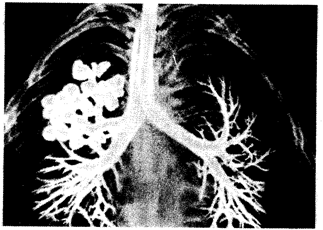

Рис. 12.1. Относительная среднестатистическая вероятность заболевания раком после однократного равномерного облучения тела дозой в 0,01 Гр в популяции людей, переживших атомную бомбардировку: 1 — лейкозы, 2 — все другие виды раковых заболеваний Хотя оценка частоты возникновения мутаций у людей встречает серьезные трудности, некоторые подходы к получению таких данных имеются. Согласно одному из них, максимальная определяемая вероятность новой мутации составляла 2,24 · 10-5 на один локус в поколении. В настоящее время давление мутационного процесса на генофонд человечества, по-видимому, усиливается благодаря росту индуцированных мутаций. Их причиной нередко служат факторы, возникающие в связи с производственной деятельностью человека в условиях научно-технической революции, например ионизирующее излучение. Подсчет прироста количества мутаций сверх фоновых значений встречается с теми же трудностями, о которых шла речь выше. Согласно ориентировочным данным, доза в 1 Гр (грей), получаемая при низком уровне радиации мужчинами, индуцирует от 1000 до 2000 мутаций с серьезными фенотипическими последствиями на каждый миллион живых новорожденных. У женщин эта цифра ниже — 900. Мутагенные факторы индуцируют мутации как в половых, так и в соматических клетках. В последнем случае результат может состоять в повышении частоты определенных заболеваний, прежде всего злокачественных опухолей. В отношении ионизирующих излучений, в частности, это лейкозы. Далее идут рак молочной железы и щитовидной железы (рис. 12.1). Численность населения планеты за обозримый исторический период в целом возросла. В эпоху неолита (10—6 тыс. лет назад) число людей было равно примерно 5 млн., в период появления городов (4,5—3,5 тыс. лет назад) — 20—40 млн., во времена Римской империи к началу новой эры — 200 млн., к 1600 г. - 500 млн., в 1800 г. -1 млрд., в настоящее время — более 6 млрд. Представляя общую тенденцию в истории человечества, эти данные указывают также на изменение во времени темпов прироста народонаселения. Этот показатель, однако, изменялся в историческом развитии неравномерно.